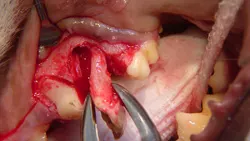

Step 8

The remaining mesial roots (the mesiobuccal and mesiopalatal roots) are separated using the same crosscut fissure bur, beginning in the furcation on the distal aspect of the remaining segment of tooth and cutting between the 2 cusps to create individual segments.

Step 9

The mesiobuccal root is elevated in much the same manner as the distal root: placing the elevator either mesial or distal to the root, twisting the elevator to apply force, and holding for 15 to 30 seconds (A). This is repeated all the way around the root segment until it is adequately loose to grasp with small extraction forceps. Extraction force is applied while gently rotating the root (B).

A

Step 10

The interradicular bone between the mesiobuccal root (now removed) and the mesiopalatal root is removed with a round ball bur (#2, friction grip) to mid level of the root (A and B). In the author's experience, performing this alveoloplasty greatly reduces the likelihood of mesiopalatal root fracture and eases extraction of this small root segment.

Step 11

Just as with the previous 2 root segments, the elevator is placed alongside the root and rotational force applied to the root segment for 15 to 30 seconds. This is repeated around the root segment until the root is loose enough to grasp with small extraction forceps. Extraction force is applied while gently twisting the root.